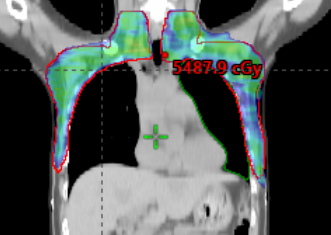

中信惠州医院肿瘤中心完成首例双侧乳腺癌放射治疗,此项技术的成功开展,标志着肿瘤中心对乳腺癌的精准治疗水平又上新的台阶。双侧乳腺癌由于解剖形态不规则,照射体积大,危及器官(肺、心脏,左前降支)受量不容易控制等诸多因素,计划设计难度大,复位要求更高。本次治疗在计划设计阶段,采用了双中心布野,评估了双拉弧,双调强野以及拉弧+IMRT衔接的治疗方式,最后综合考虑左臂无法充分上举的实际情况,最终采用左侧IMRT+右侧拉弧的放疗技术,肺、心脏,左前降支等危及器官限值均在要求范围内,处方剂量为5000cGY/200cGY,每次治疗前均实施CBCT进行位置校准。病人于2024年2月22日至2024年3月27日顺利完成放疗,无明显严重放射性皮肤反应。